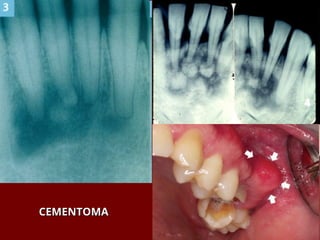

 Cementoma – Displasia Cementossea

CEMENTOMA

TUMORES ODONTOGÊNICOS TUMORES ODONTOGÊNICOS Ameloblastoma Ameloblastoma  Cementoma – Displasia Cementossea Cementoma – Displasia Cementossea Focal Focal  Odontoma Odontoma